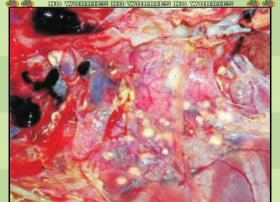

如何防治肉鸡腹水综合征

肉鸡腹水综合征,这个名词对于许多从事养殖业的人来说,无疑是一个沉重的负担。它像一场无形的瘟疫,悄然侵袭着鸡群,带来巨大的经济损失。然而,防治此病并非无计可施。只要我们深入了解其病因,细心观察症状,精确把握病理变化,并采取有效的防治措施,就能